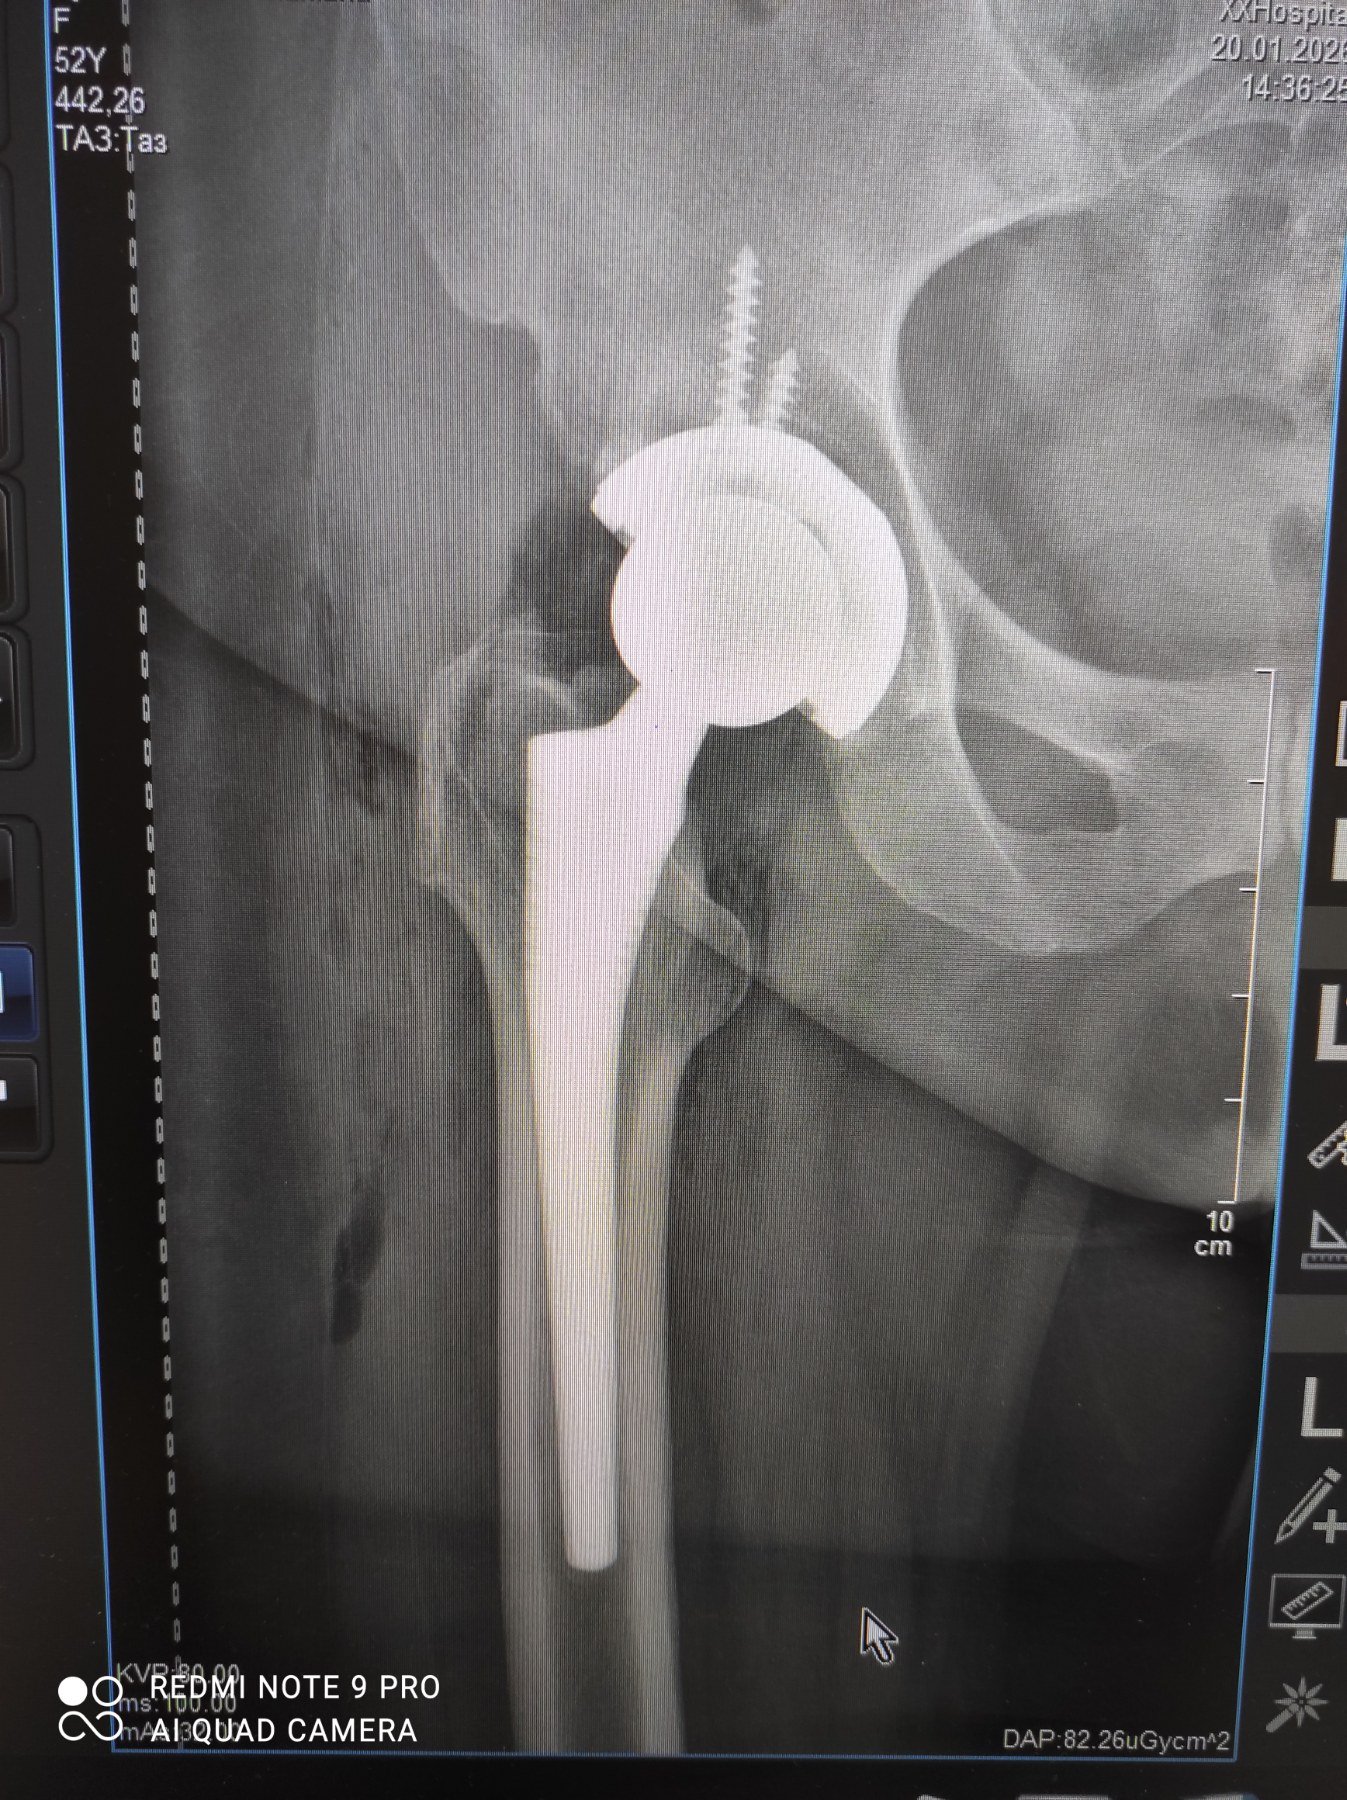

Від щирого серця хочу подякувати хірургу Досяк Мирославу Ігоровичу. Я щиро бажаю Вам успішно продовжувати рятувати своїх пацієнтів, завжди виправдовувати всі добрі надії і неодмінно знаходити вихід з будь-якої ситуації. Здоров’я Вам і Вашій родині, благополучної діяльності і щасливого довгого життя. Спасибі за Вашу працю, за Ваш професіоналізм, за Вашу самовідданість. Також хочу висловити вдячність медсестрі, яка по операції цілу ніч не відходила від мене і зволожувала мої губи. А ще, велике спасибі інтерну Тарасу, який зустрів при поступленні і поміг зробити всі необхідні аналізи в одному кабінеті,щоб не мучити мене,перед операцією. Велике дякую анастазіологу який професійно виконав свою роботу і врахував попередні травми. Загалом Хочу висловити величезну подяку всім працівникам лікарні від санітарочки до хірурга, там працюють чудові люди, які люблять свою професію. Дякую1-ій МІСЬКІЙ КЛІНІЧНІЙ ЛІКАРНІ ІМ. КНЯЗЯ ЛЕВА за Ваших відданих і чуйних професіоналів, за безкоштовні медикаменти та добро, яке вони випромінюють в своїй роботі. А також за чистоту!